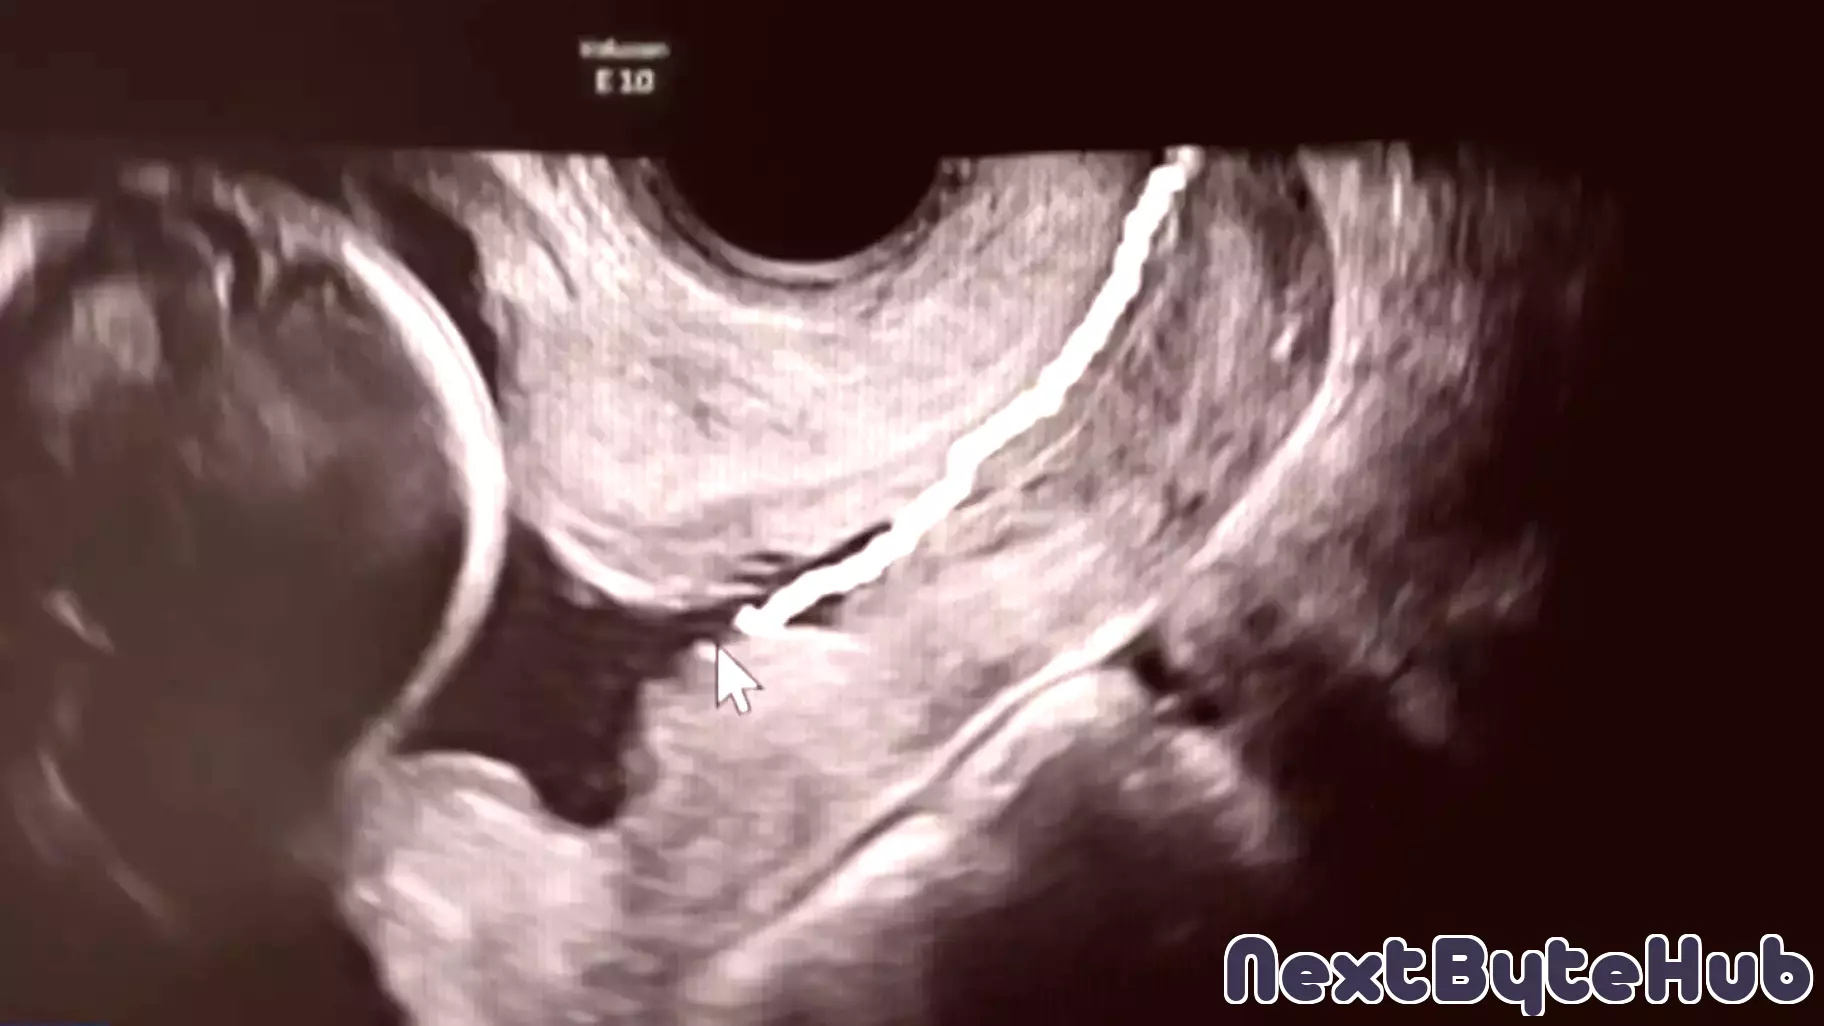

Researchers at Columbia University are pioneering new technology aimed at monitoring pregnancy, with a focus on preventing premature births. This innovative approach seeks to enhance the understanding of pregnancy health and improve outcomes for both mothers and infants. By leveraging advanced monitoring techniques, the technology aims to provide real-time data that can help healthcare professionals identify potential complications early on.

The initiative is part of a broader effort to address the rising rates of premature births, which can lead to serious health issues for newborns. The research team is exploring various methods to track vital signs and other important health indicators throughout pregnancy. This could empower expectant mothers and their healthcare providers to take proactive measures, ensuring a safer pregnancy journey.

As the project progresses, the implications for maternal and infant health could be significant, potentially transforming how pregnancies are monitored and managed in clinical settings. The commitment to developing such technology reflects a growing recognition of the importance of maternal health in public health discussions.